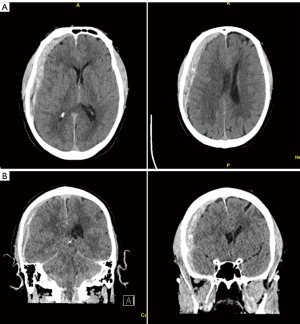

A non-contrast head computed tomography (CT) obtained at the time demonstrated posterior fossa crowding with effacement of the ambient cisterns, and a diffuse appearance of brain edema with slit like ventricles. There was also a small tentorial SDH and small amount of intraventricular hemorrhage. There was no evidence of bony fractures or complications from head tong sites (Figure 2). There had been no episodes of hypoxia during or after the procedure.

Beta-2 transferrin levels (a highly sensitive and specific measure of CSF) from drain fluid were negative postoperative days 1–4, with total daily drain output 652, 147.5, 216, and 98 mL but when there was a sudden increase in serous quality drainage in the subfascial drain on postoperative day 5 with the patient reporting a minor eye pain with output of 158 mL. Another beta-2 transferrin lab was sent and this time it was positive, as a result the drain was pulled and the drain site was oversewn. The patient passed head of bed trials and never experienced proto-typical symptoms of CSF leak. Repeat head CT postoperative day 4 demonstrated marked improvement in ventricular caliber and cisternal effacement, slightly decreased intraventricular blood products but no other significant changes with regards to subdural and parafalcine hemorrhages (Figure 3).

While the patient was being weaned from anesthesia, he was noted to be demonstrating seizure-like convulsions. Propofol was re-initiated with resolution of clinical seizure activity. The patient was taken to emergent noncontrast head CT which demonstrated a right SDH with 7–8-mm midline shift (Figure 6). Neurosurgery was consulted for further management and the patient was loaded with levetiracetam, and was brought to the operating room (OR) with neurosurgery for emergent craniotomy and hematoma evacuation.

It is imperative that imaging and clinical presentation are recognized promptly to ensure proper treatment. Head CT shows findings often interpreted as hypoxic brain injury, with an appearance of diffuse brain edema. This finding may be in part secondary to brain sag in the setting of CSF hypovolemia/hypotension with resulting venous engorgement (17). Diffuse brain edema on imaging would typically prompt clinicians to elevate the head of the patient’s bed, but in these cases, head of bed elevation could lead to progressive and potentially irreversible worsening due to increasing brain sag, herniation, and brainstem compression. As seen in our cases, a flat head-of-bed position should be maintained in this situation.